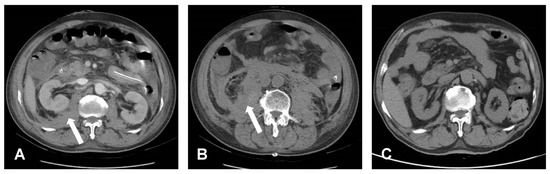

2. Illustrative Case